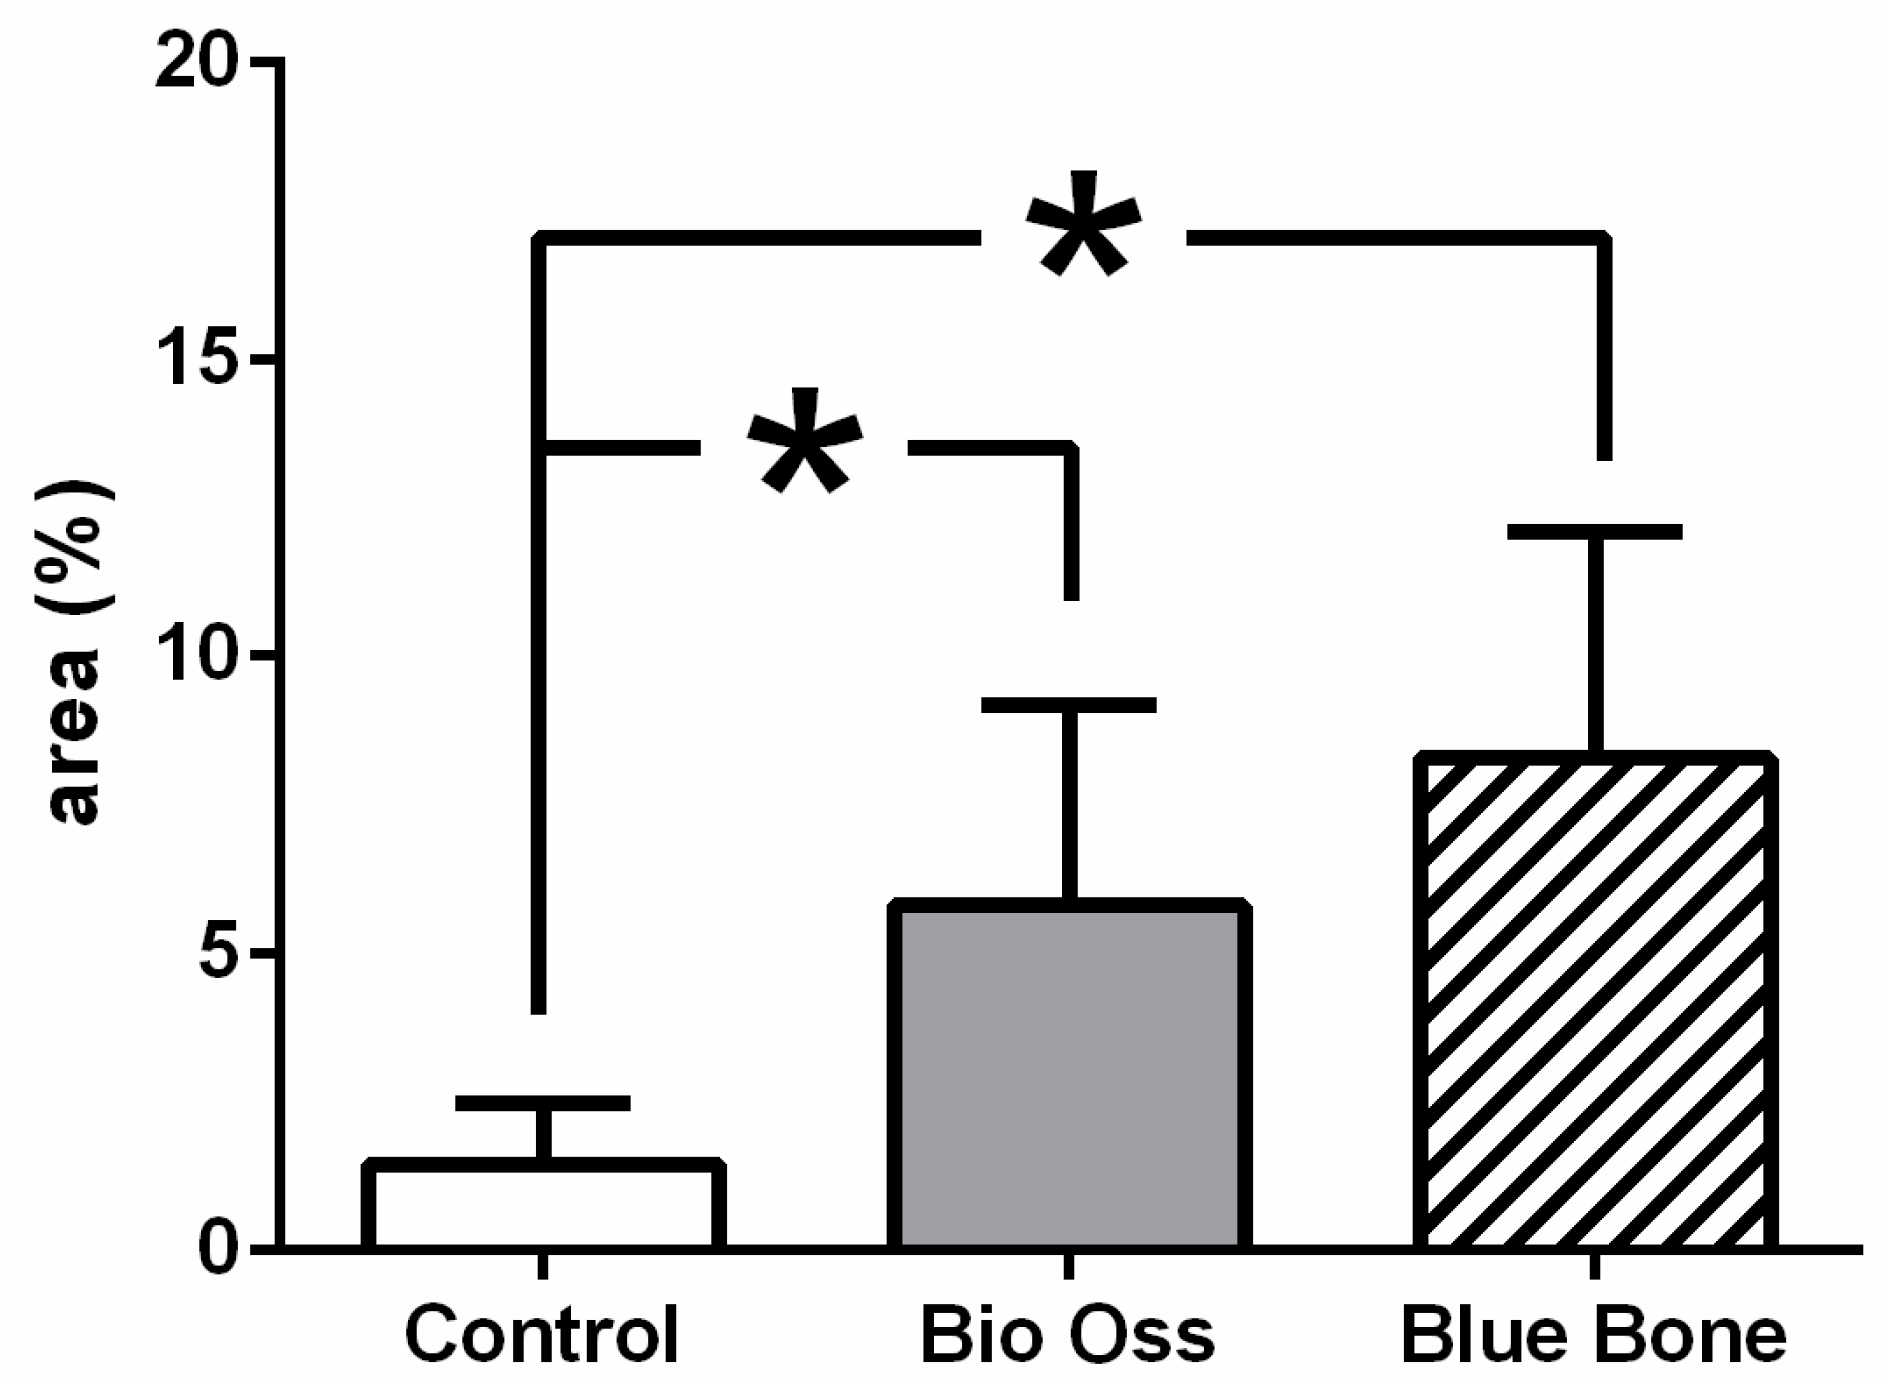

3.2. Osteopontin

3.3. Vascular Endothelial Growth Factor (VEGF)

- The response of the extracellular matrix protein (osteopontin) was similar in the synthetic nano-hydroxyapatite and xenogeneic hydroxyapatite groups compared to the control group.

| Kruskal–Wallis Test | |||

|---|---|---|---|

| Mean | 1.447 | 5.804 | 8.279 |

| Std. Deviation | 1.024 | 3.36 | 3.823 |

| p value | 0.0072 | ||

| Exact or approximate p value? | Exact | ||

| p value summary | *** | ||